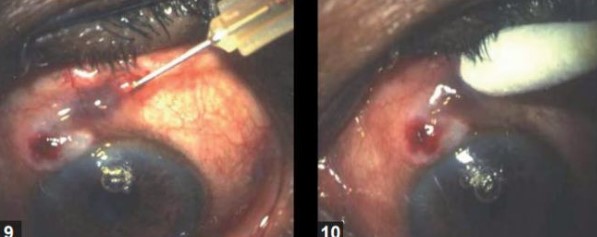

๐ชก 2. Needle Revision (NR)

- Uses a 26G needle to physically break adhesions under the conjunctiva

- Expands the bleb space and restores outflow

- Often combined with 5-FU injections to suppress fibrosis